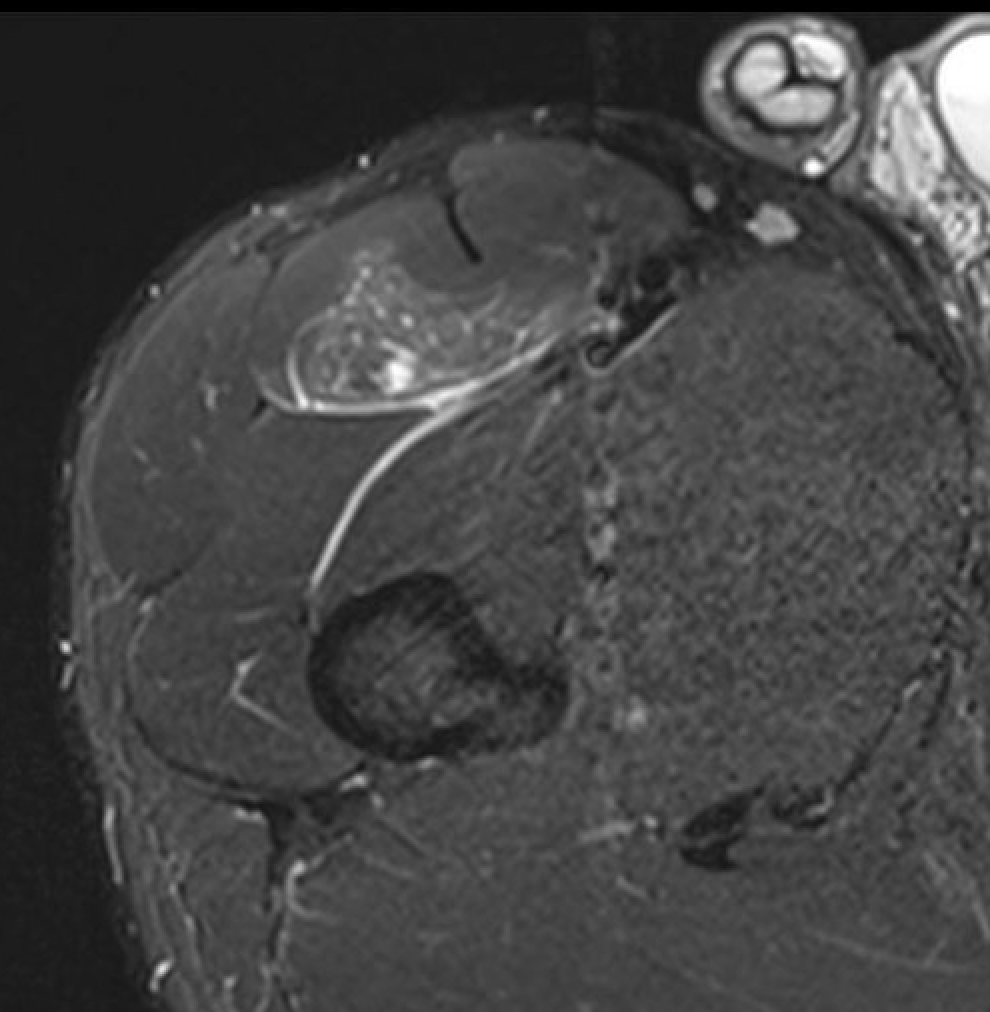

Quadriceps muscle tears